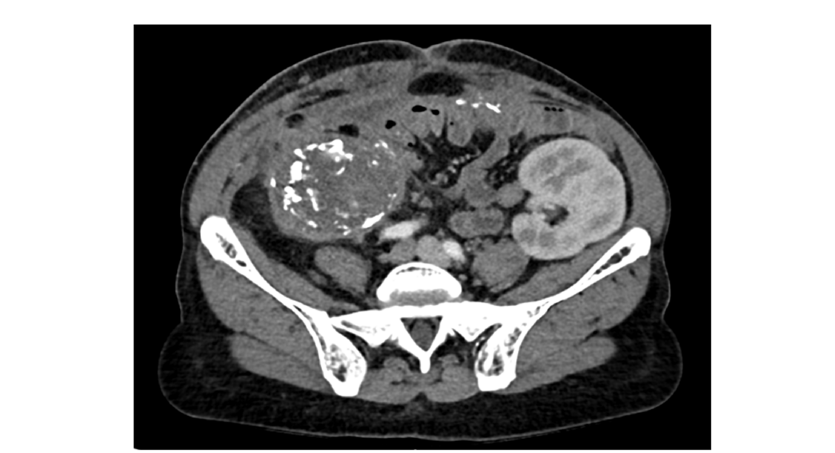

A 40-year-old female with two prior renal transplants presented for a second surgical opinion on a fistula from her failed renal transplant. A native of Liberia, she had moved to the US in 2001. Her end stage renal disease was secondary to longstanding hypertension and her medical history was notable for hyperlipidemia and chronic Hepatitis B infection. Her first renal transplant (right sided) was performed in 2004. This was complicated by rejection leading to graft failure and hemodialysis dependence from 2010 until 2023. In September 2023, she received a second deceased donor kidney transplant (left sided) without complications and with sustained excellent function on an immunosuppression regimen of Tacrolimus, Mycophenolate Mofetil and Prednisone. In December 2024, she developed a draining renocutaneous fistula with infection of her nonfunctioning (right sided) graft. Cultures performed from this drainage grew Salmonella enterica. Initial treatment was with Doxycycline and an attempt at graft nephrectomy that was aborted intra-operatively due to dense adhesions. By May of 2025, she was transitioned to Amoxicillin due to increased drainage despite ongoing suppressive therapy with Doxycycline. Repeat CT imaging performed at our center in June 2025 showed a heavily calcified graft with emphysematous pyelitis (Figure 1). As part of her workup, blood and stool cultures were negative and Strongyloides and Schistosoma serologies were negative. After informed consent regarding surgery and risks, she successfully underwent en bloc graft nephrectomy, appendectomy (due to adhesions) and tract excision. Intraoperative cultures from the resected renal parenchyma were positive for Salmonella spp, type D. Pathology revealed diffuse necrosis with abscess formation in the right transplanted kidney and fistula formation with necrosis and fibrosis (Figure 2). Initial antibiotic therapy at our center was with Ceftriaxone, then broadened to Meropenem based on susceptibilities. Finally, she completed a 14-day course of oral TMP/SMX prior to discharge. She had an uneventful post-operative course. After 6 weeks post-surgery, she was asymptomatic with a well healed wound.

Figure 1:Calcified failed right transplant kidney. calcified, non/hypo-enhancing right failed kidney parenchyma with surrounding fat stranding.